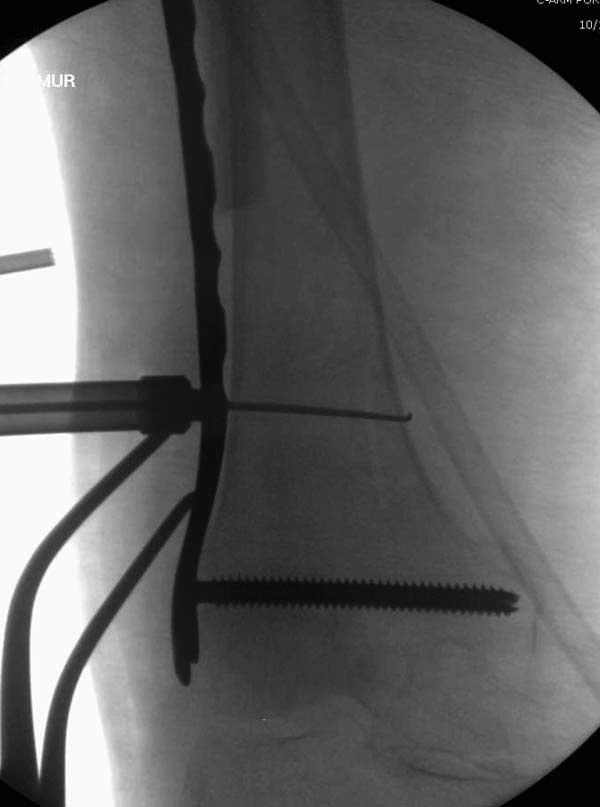

Такие “чужие осложнения” встречаются у всех и представляю банальный случай, который шаг за шагом показано как перерос в более сложный процесс... Больная 70 лет, множественные ко-морбидности, чрезвертельный перелом первоначально фиксирован Гамма 3. Осложнение в течение 6 недель, ревизия тотальной артропластикой и во время установки ножки обнаружена трещина диафиза (17), из малого доступа фиксация алло-графтом.

Обычно после чрезвертельных переломов, за исключением молодых, у пожилых остается нестабильность при движении. Часто падают и после 3х мес. в результате падения обнаружен перипротезный перелом (22-23), который зафиксирован Синтез пластиной.

Повторно поступает после двух с половиной лет, где обнаруживается перелом на второй стороне. Немного сложно, но для фиксации выбрали Antegrade InterTan Smith Nephew Nail и с момента фиксации более 3х мес.